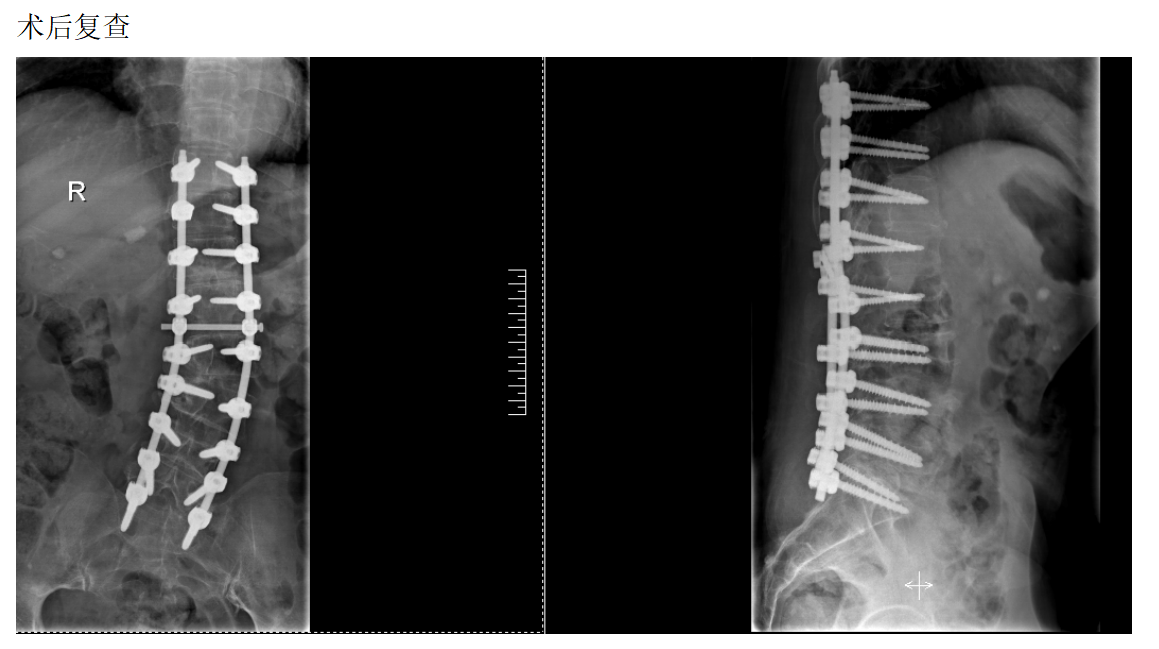

脊柱外科组(骨折、畸形、复杂融合固定)

脊柱畸形病历

主诉:腰部疼痛伴间歇性跛行10余年

现病史:患者10余年前无明显诱因出现腰部疼痛伴间歇性跛行,左侧较重,多于行走100米后症状加重,至当地医院诊治,考虑"腰椎间盘突出症"。给予药物对症治疗,膏药等,效果欠佳。今日为求进一步诊治,来我院椎间盘科,以“脊柱侧弯畸形,腰椎间盘突出症”为诊断收住我科。发病以来,神志清楚,精神尚可,饮食正常,睡眠一般,体力正常,大小便正常。